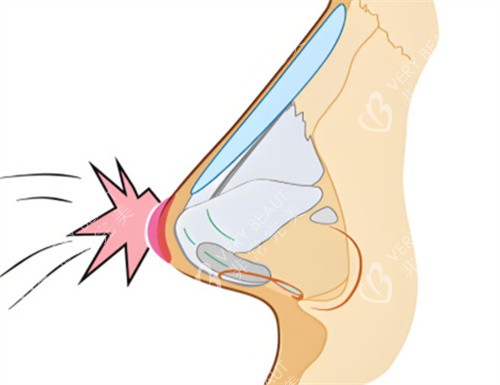

•单侧耳软骨硅胶假体隆鼻:价格区间约为6480元至8800元。该方案通常是将自体耳软骨与硅胶假体结合使用,旨在利用耳软骨对鼻尖部位进行塑形,以期获得更自然的支撑和触感,同时可能降低单纯使用假体带来的透光或移位风险。